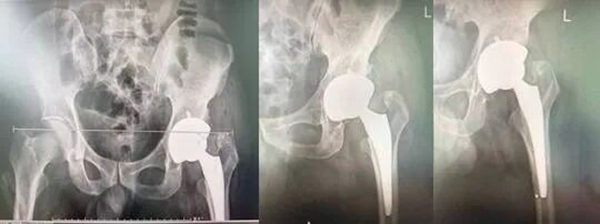

术后复查X线检查:

在完善各项术前准备后,由孙利副主任医师主刀,骨科团队为患者实施左侧全髋关节置换术。手术过程十分顺利,术中精准置入人工髋关节假体,同时严格校准下肢长度,成功将患者短缩的左腿恢复至与右腿等长,彻底解决了跛行隐患。